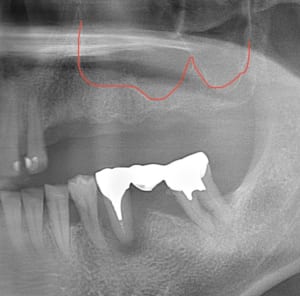

↑赤字の上の空間はもう鼻腔になってしまうのでここにインプラントを入れることはできません。

そこで

鼻腔のシュナイダー膜を挙上した上で

顎骨の側面から人工骨を補う必要が出てきます。

これでインプラントの長さ10mm近くのインプラントも余裕で入れる骨の高さが確保できました。